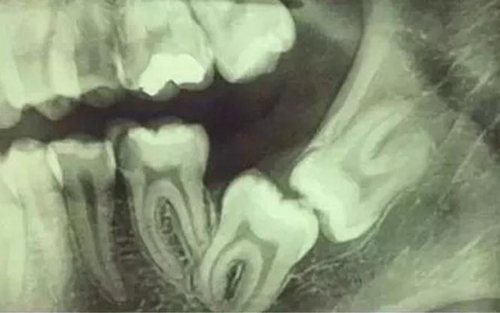

根神經(jīng)線位置千變?nèi)f化,有些離智齒牙根很遠(yuǎn),有些很近,有些甚至穿過智齒根部。

拍片是為了了解智齒周圍情況,也是為了了解智齒結(jié)構(gòu),牙根結(jié)構(gòu)千變?nèi)f化,有可能是融合成一個根,也可能是八爪根。不同牙根不同位置及方向,只有通過拍片來確認(rèn)。

通過拍片可以了解牙齒本身:生長方向,牙根數(shù)目,牙根是否彎曲,膨大等。

與重要解剖結(jié)構(gòu)的位置關(guān)系:如上頜磨牙與上頜竇的關(guān)系;下頜磨牙與下頜神經(jīng)管的關(guān)系;兒童在混合牙列期恒牙與乳牙胚的關(guān)系等??梢詼p少拔牙的風(fēng)險。